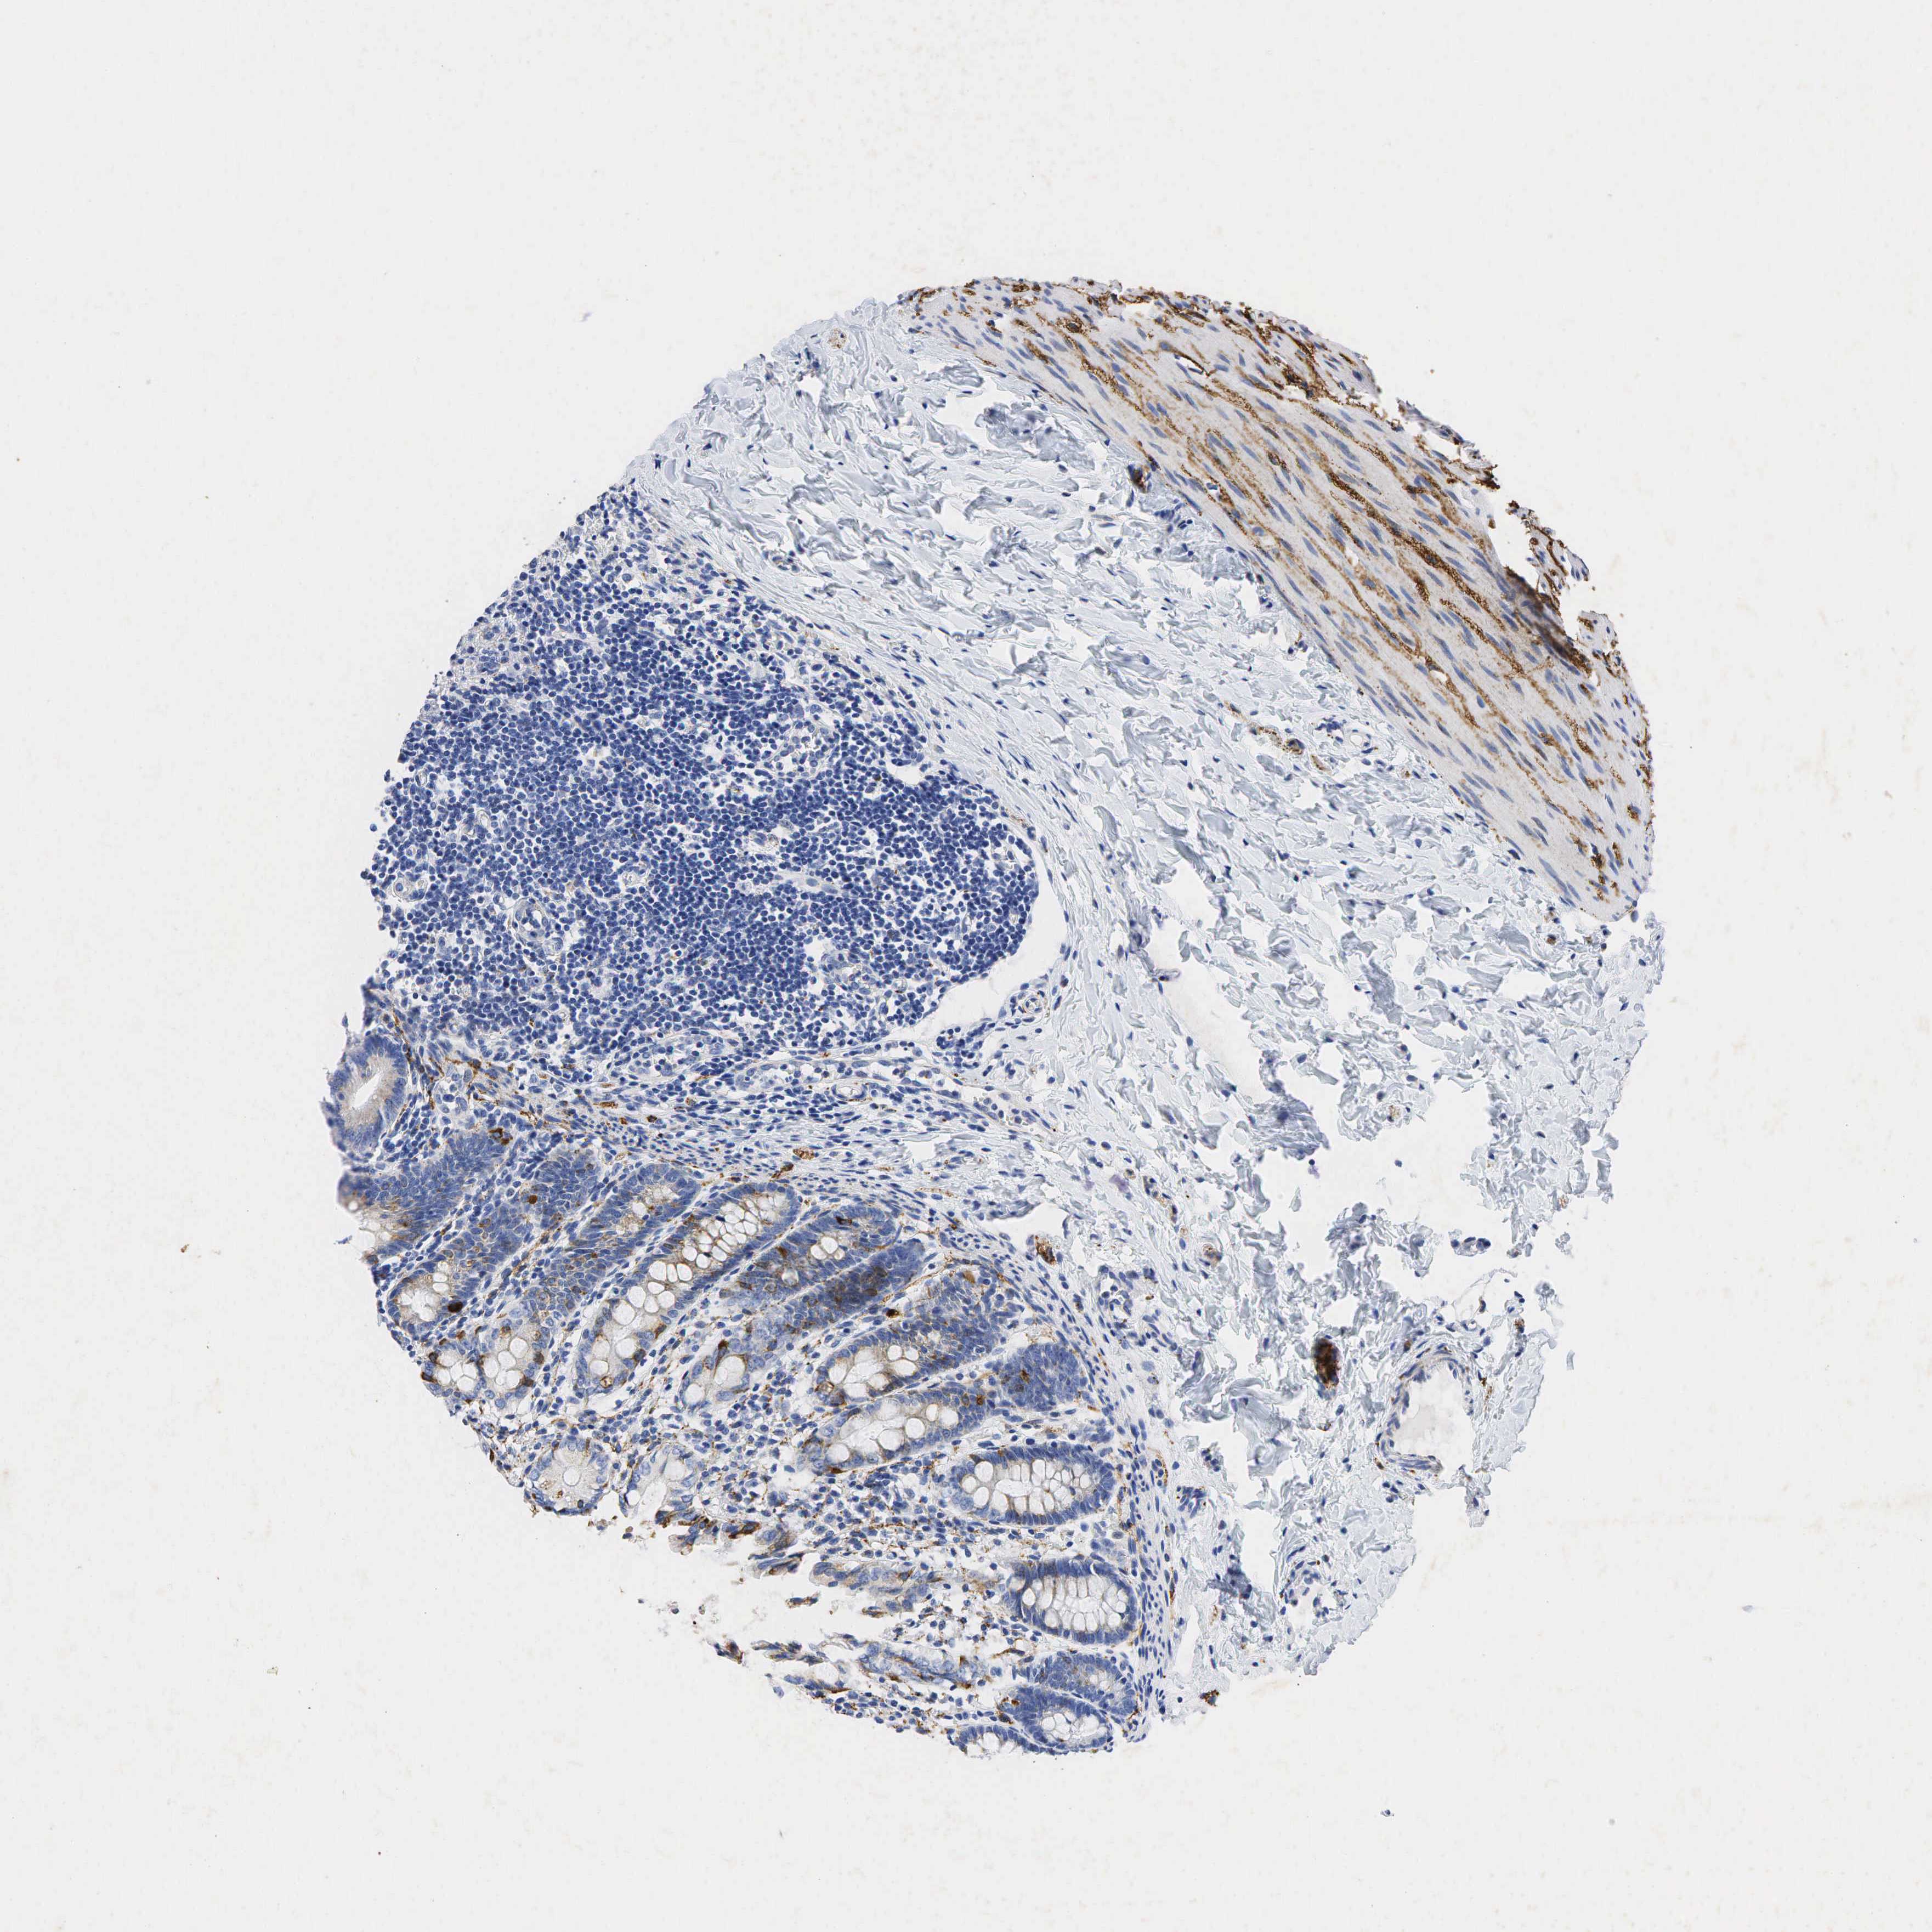

SYP